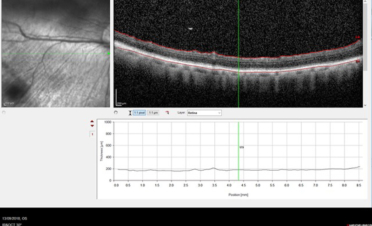

Haremos una OCT del segmento posterior cuando necesitemos:

- Medir las diferentes capas de fibras de la retina y el nervio óptico. Con este tipo de OCT realizamos un corte histológico en vivo de las diferentes capas del fondo ocular: retina, nervio óptico y coroides pudiendo llegar incluso hasta la esclerótica.

- Valorar cambios en la estructura, como por la presencia de exudados, hemorragias, degeneraciones,

edema, membranas epirretinianas, anomalías del vítreo posterior ….